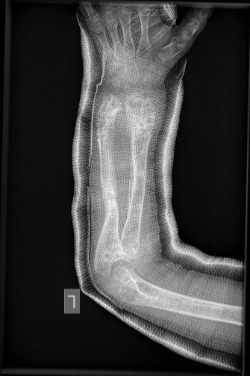

Οι εικόνες απεικονίζουν περιστατικό με πολλαπλά οστεοχονδρώματα, το οποίο χειρουργήθηκε από τον Δρ. Ζένιο.

Προ-εγχειρητικά

Μετ-εγχειρητικά